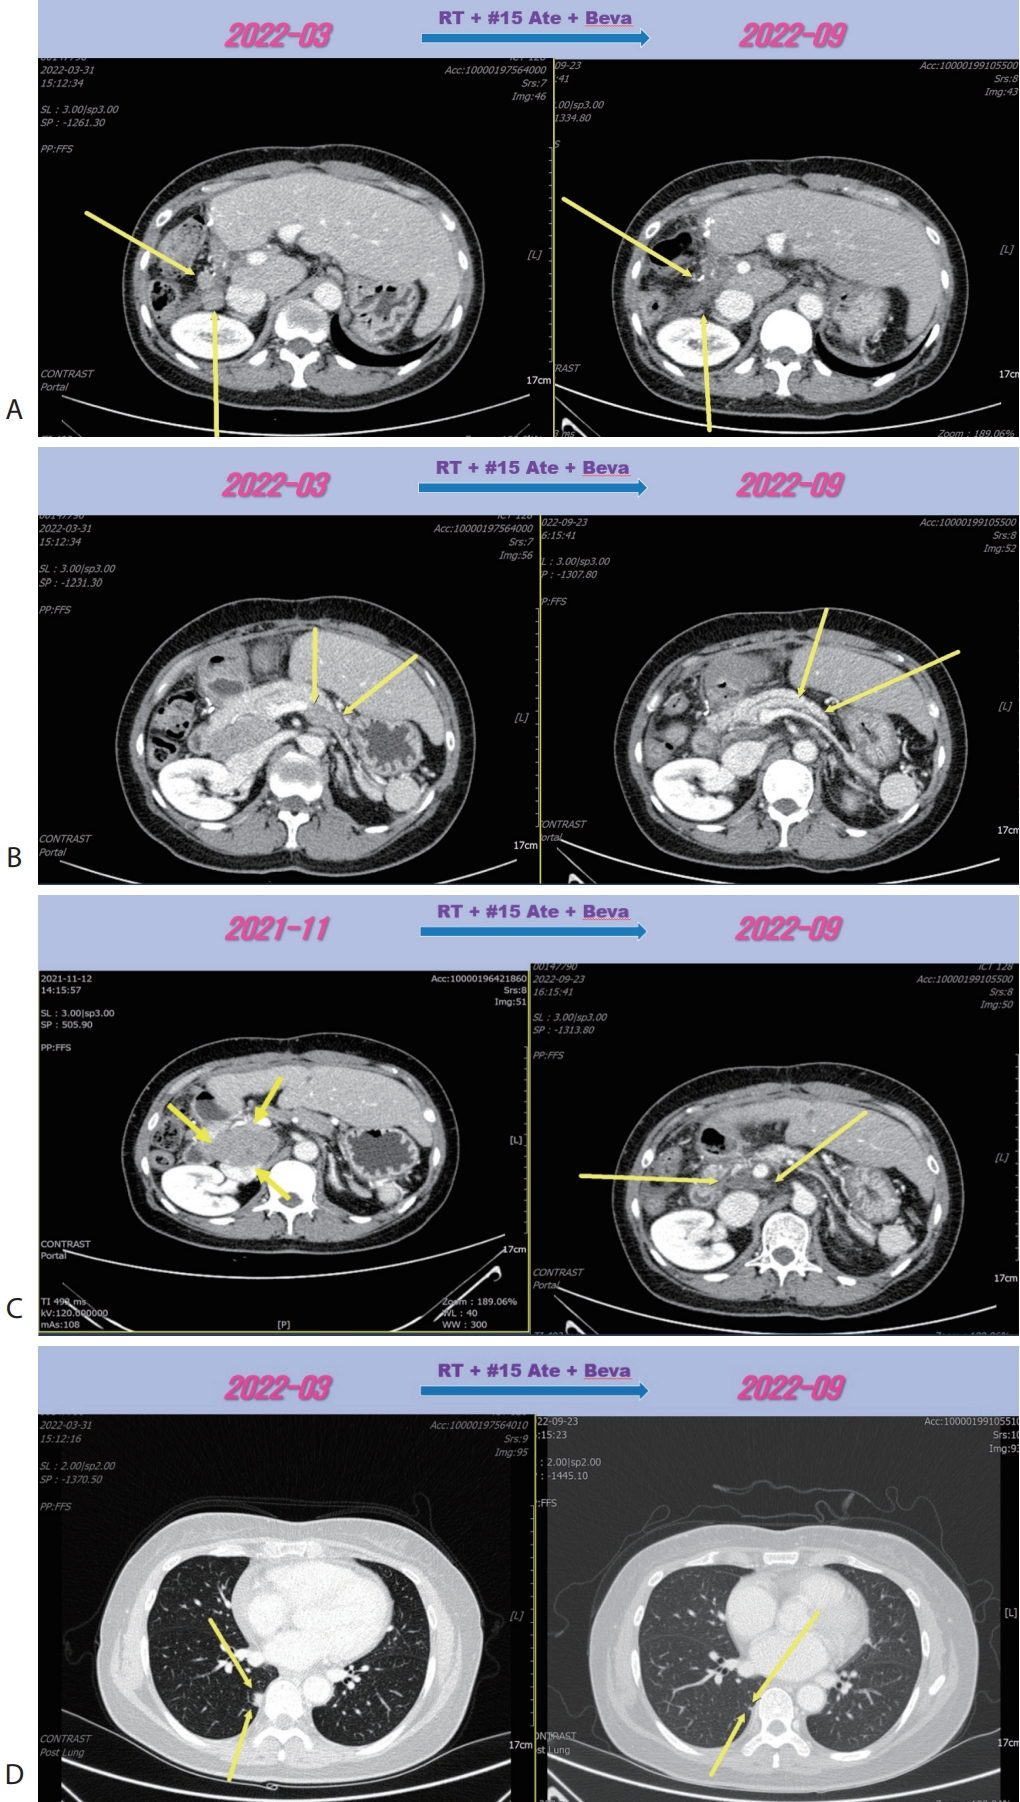

D). We concluded this mixed response as an oligo-progression and treated the patient with same systemic therapy (Ate+Beva) combining radiotherapy (RT) for prerenal LN metastasis (45 Gray/25 fraction). In follow-up CT scan that was conducted 6 months after commencing Ate+Beva plus RT, abdominal increasing LN metastasis previously was markedly shrinked (

Fig. 3A–

C) and lung metastasis was nearly disappeared (

Fig. 3D) and levels of AFP and PIVKA-II were normalized. We completed total thirty-two cycles of Ate+Beva for 2 years and we did not proceed further cycles of Ate+Beva because national medical insurance for Ate+Beva was terminated. At the time of stopping Ate+Beva, nearly CR state of tumor had been still maintained. However left inguinal & pelvic LN metastasis was recurred after 6 months from stopping Ate+Beva (

Figure 3.Liver CT scan (A–C) and chest CT scan (D) after combination therapy of RT and fifteen cycles of 1st line Ate+Beva. Increasing peritoneal and lymph node metastasis were shrinked (A, B). Especially although RT was irradiated to only the prerenal lymph node metastasis (A), out-field site of RT such as peripancreatic (B), largest portocaval lymph node metastasis (C) and new onset lung metastasis (D) were markedly improved. CT, computed tomography; RT, radiotherapy; Ate+Beva, atezolizumab plus bevacizumab.